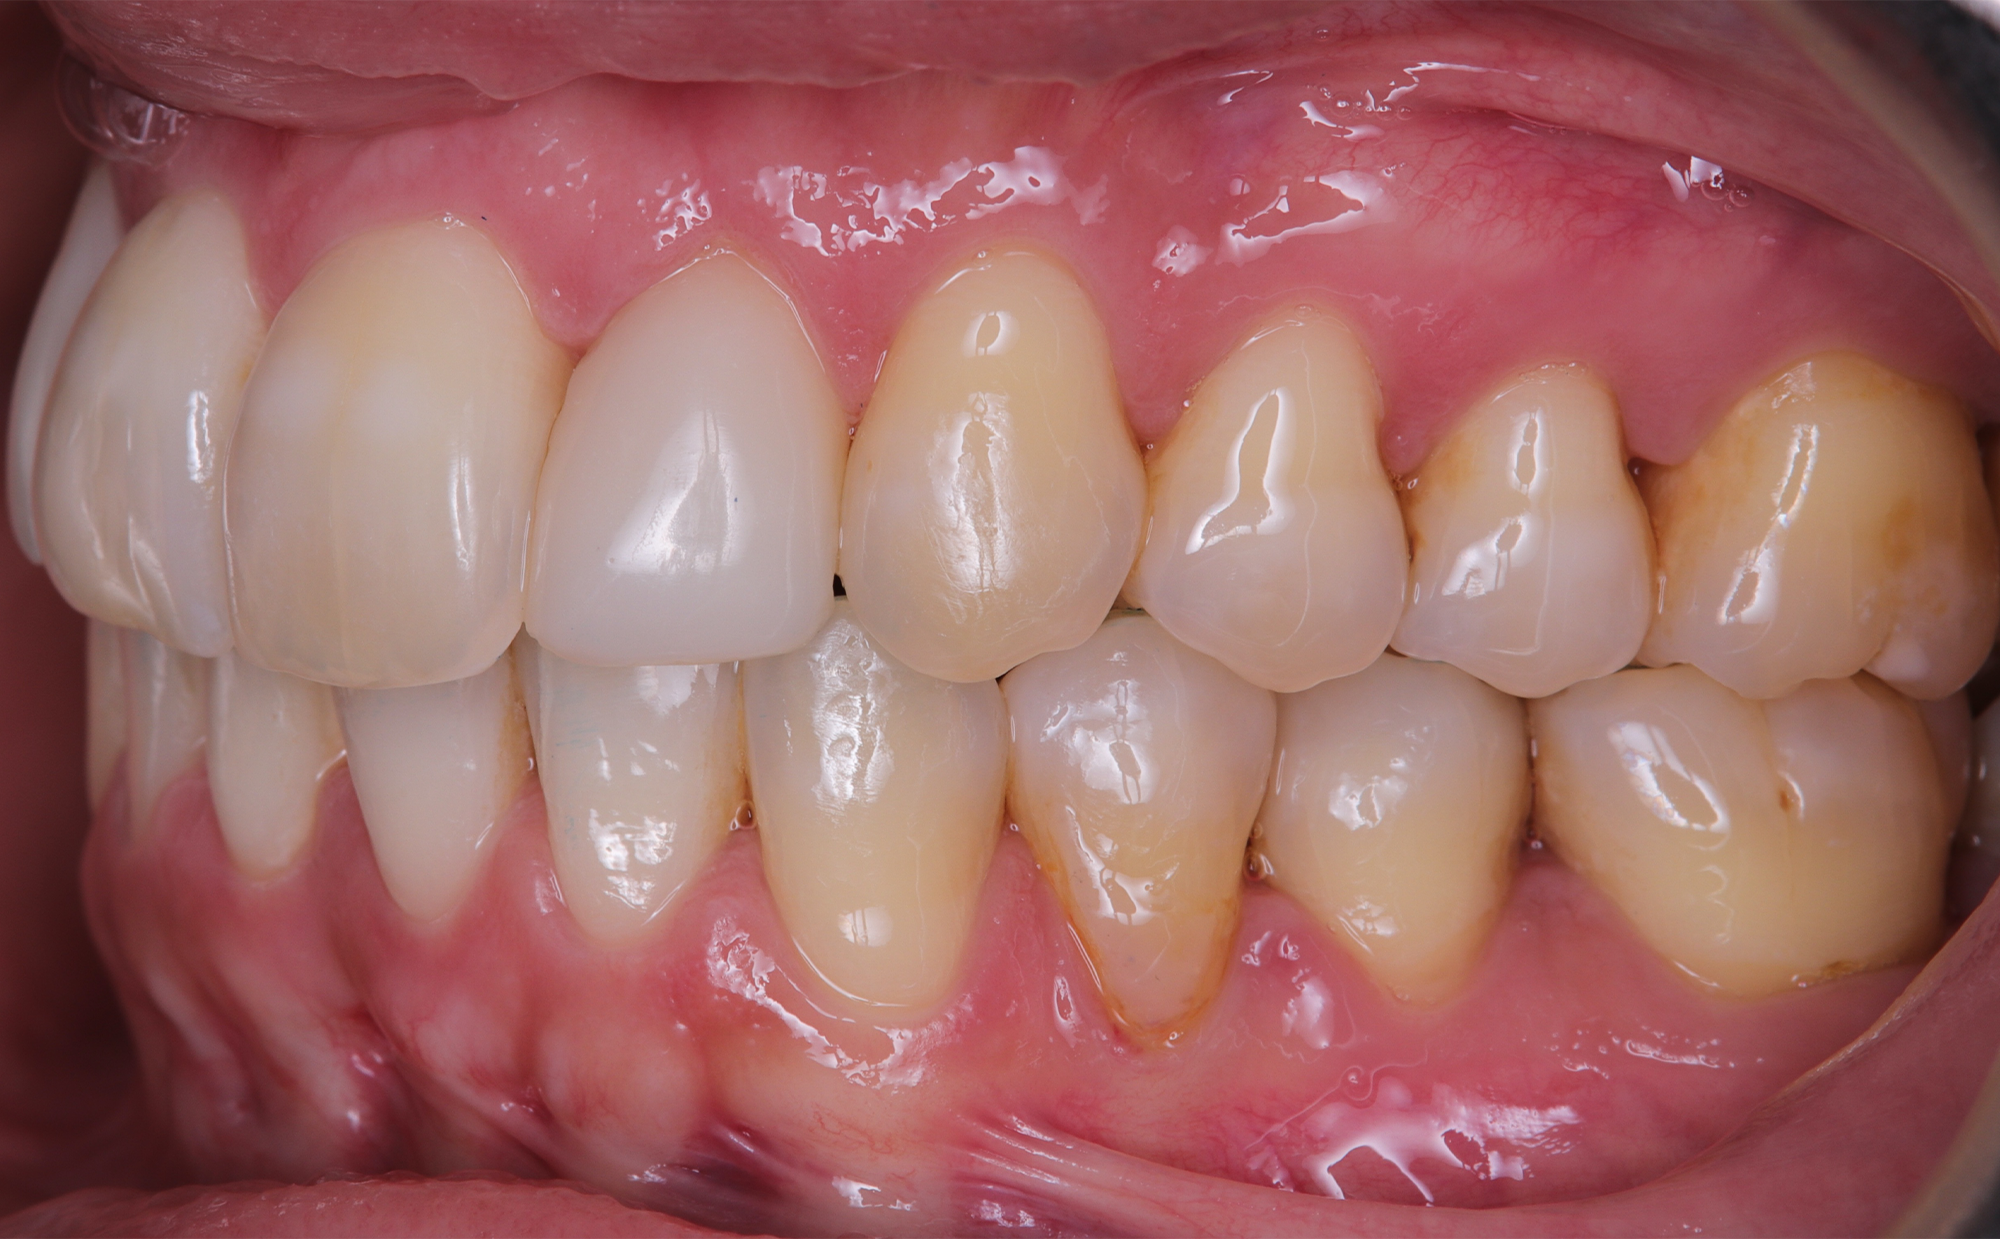

At the conclusion of the treatment, the patient achieved excellent dental alignment and a stable occlusal relationship, particularly in the anterior region. Radiographs and clinical assessments confirmed that there was no further bone loss and that previous improvements were maintained. The aesthetic enhancement from the composite restorations further contributed to the overall success of the treatment.

This case report demonstrates that in patients with a history of periodontal treatment, a carefully modulated orthodontic plan—characterized by reduced tooth movement speed and light forces—can successfully address issues of crowding and anterior crossbite while stabilizing the occlusion and supporting tissues. The favorable outcome achieved with the Spark Advanced system, along with strategic IPR and restorative composite application, supports the adoption of conservative orthodontic protocols focused on occlusal and tissue stability.